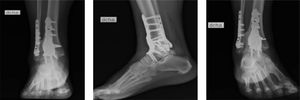

Caso 1El primer caso trata de una paciente de sexo femenino de 33 años de edad, obesa y sin otras comorbilidades que sufre un accidente de tránsito con posterior aplastamiento del tobillo derecho por su motocicleta. Ingresa con dolor intenso, deformidad evidente, impotencia funcional y con estado de la piel y neurovascular distal conservado. Se diagnostica una luxofractura bimaleolar de tobillo, con pérdida de reducción tibiotalar y fracturas de maléolo lateral (clasificación de Denis-Weber B7) y maléolo posterior (clasificación Bartonicek II8). Se intenta una reducción inicial cerrada la cual resulta insatisfactoria por lo que ingresa a pabellón para reducción cerrada bajo anestesia en la cual la reducción tibiotalar es laboriosa e inestable. Se instala un fijador externo en configuración delta.

La paciente queda hospitalizada, realizándose una TC (figura 1) durante la hospitalización. La lesión de Bosworth no fue diagnosticada en forma inmediata, solo en la TC postoperatorio se observa la interposición del fragmento de fíbula en el rasgo de fractura del maléolo posterior como causa de la irreductibilidad. Durante la espera de disponibilidad de pabellón para resolución definitiva, a los dos días de la lesión inicial, la paciente comienza con dolor intenso, desproporcionado, al examen físico destaca dolor ante la flexión del hallux, por lo que se le diagnostica un síndrome compartimental e ingresa a pabellón para una fasciotomía de emergencia.

Dos días después de fasciotomía se realiza una reducción abierta y osteosíntesis con tornillos y placa mediante un abordaje posterolateral, desimpactando el fragmento proximal de la fíbula que queda atrapado en el maléolo posterior para luego reducir y osteosintetizar con placa el maléolo posterior, seguido de una reducción y osteosíntesis con placa anatómica para el maléolo lateral asociado a un tornillo desde la fíbula a la tibia de manera tricortical para mantener la reducción de la sindesmosis (figura 2).

. Radiografías de tobillo posterior a reducción abierta y fijación interna. Proyección en mortaja, lateral, anteroposterior (AP). Imágenes post quirúrgicas luego de segunda intervención con reducción y osteosíntesis de fíbula y maléolo posterior con placas e fijación rígida de la sindesmosis.